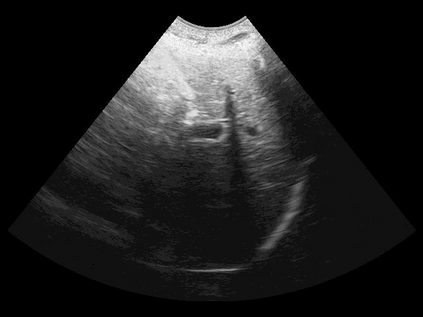

Most deep neural networks (DNNs) based ultrasound (US) medical image analysis models use pretrained backbones (e.g., ImageNet) for better model generalization. However, the domain gap between natural and medical images causes an inevitable performance bottleneck. To alleviate this problem, an US dataset named US-4 is constructed for direct pretraining on the same domain. It contains over 23,000 images from four US video sub-datasets. To learn robust features from US-4, we propose an US semi-supervised contrastive learning method, named USCL, for pretraining. In order to avoid high similarities between negative pairs as well as mine abundant visual features from limited US videos, USCL adopts a sample pair generation method to enrich the feature involved in a single step of contrastive optimization. Extensive experiments on several downstream tasks show the superiority of USCL pretraining against ImageNet pretraining and other state-of-the-art (SOTA) pretraining approaches. In particular, USCL pretrained backbone achieves fine-tuning accuracy of over 94% on POCUS dataset, which is 10% higher than 84% of the ImageNet pretrained model. The source codes of this work are available at https://github.com/983632847/USCL.

翻译:大部分深心神经网络(DNNS)基于超声波(美国)的超声波医学图像分析模型使用预先训练的脊椎(如图像网络)来进行更好的模型化分析。然而,自然图像和医疗图像之间的领域差距造成了不可避免的性能瓶颈。为了缓解这一问题,为在同一领域直接训练建造了一个名为US-4的美国数据集。该数据集包含来自四个美国视频子数据集的23 000多张图像。为了从美国-4中学习强健的特征,我们提议了美国半监督的对比学习方法,名为USCL(USCL),用于预培训。为了避免负面对子与有限的美国视频中丰富的地雷视觉特征之间的高度相似性,USCL采用了一种样品配对生成方法来丰富单步对比性优化所涉及的特征。关于一些下游任务的广泛实验显示了USCL对图像网络预培训和其他状态艺术预培训方法的优势。特别是,USCLU预先训练的骨架在POCS数据集上实现了94 %的微调精准性精确度,这在图像网络上比84%高10 %/MUSPASTASTASTRAIN premstrain practresmex pract press press rodustrismex sramduction sramduction sramduction sramduction surgles)。